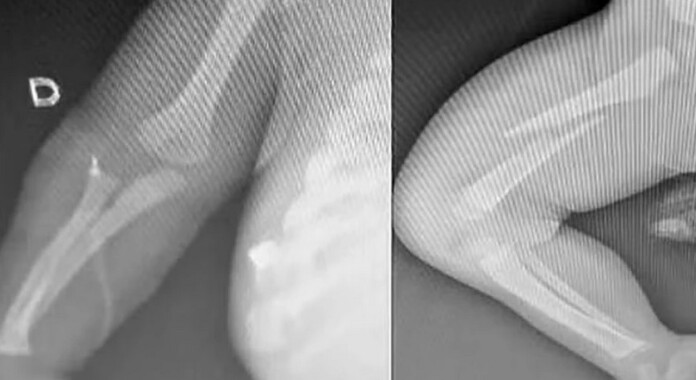

Confrontado pelas autoridades, o homem confessou que agrediu a criança porque ela não parava de chorar. O bebê foi levado à Santa Casa desmaiado, apresentando fraturas nos braços, fêmur, costela e perfuração pulmonar, além de vários hematomas. A polícia acionou o Conselho Tutelar e, após a confissão do pai, ele foi preso em flagrante por lesão corporal grave.